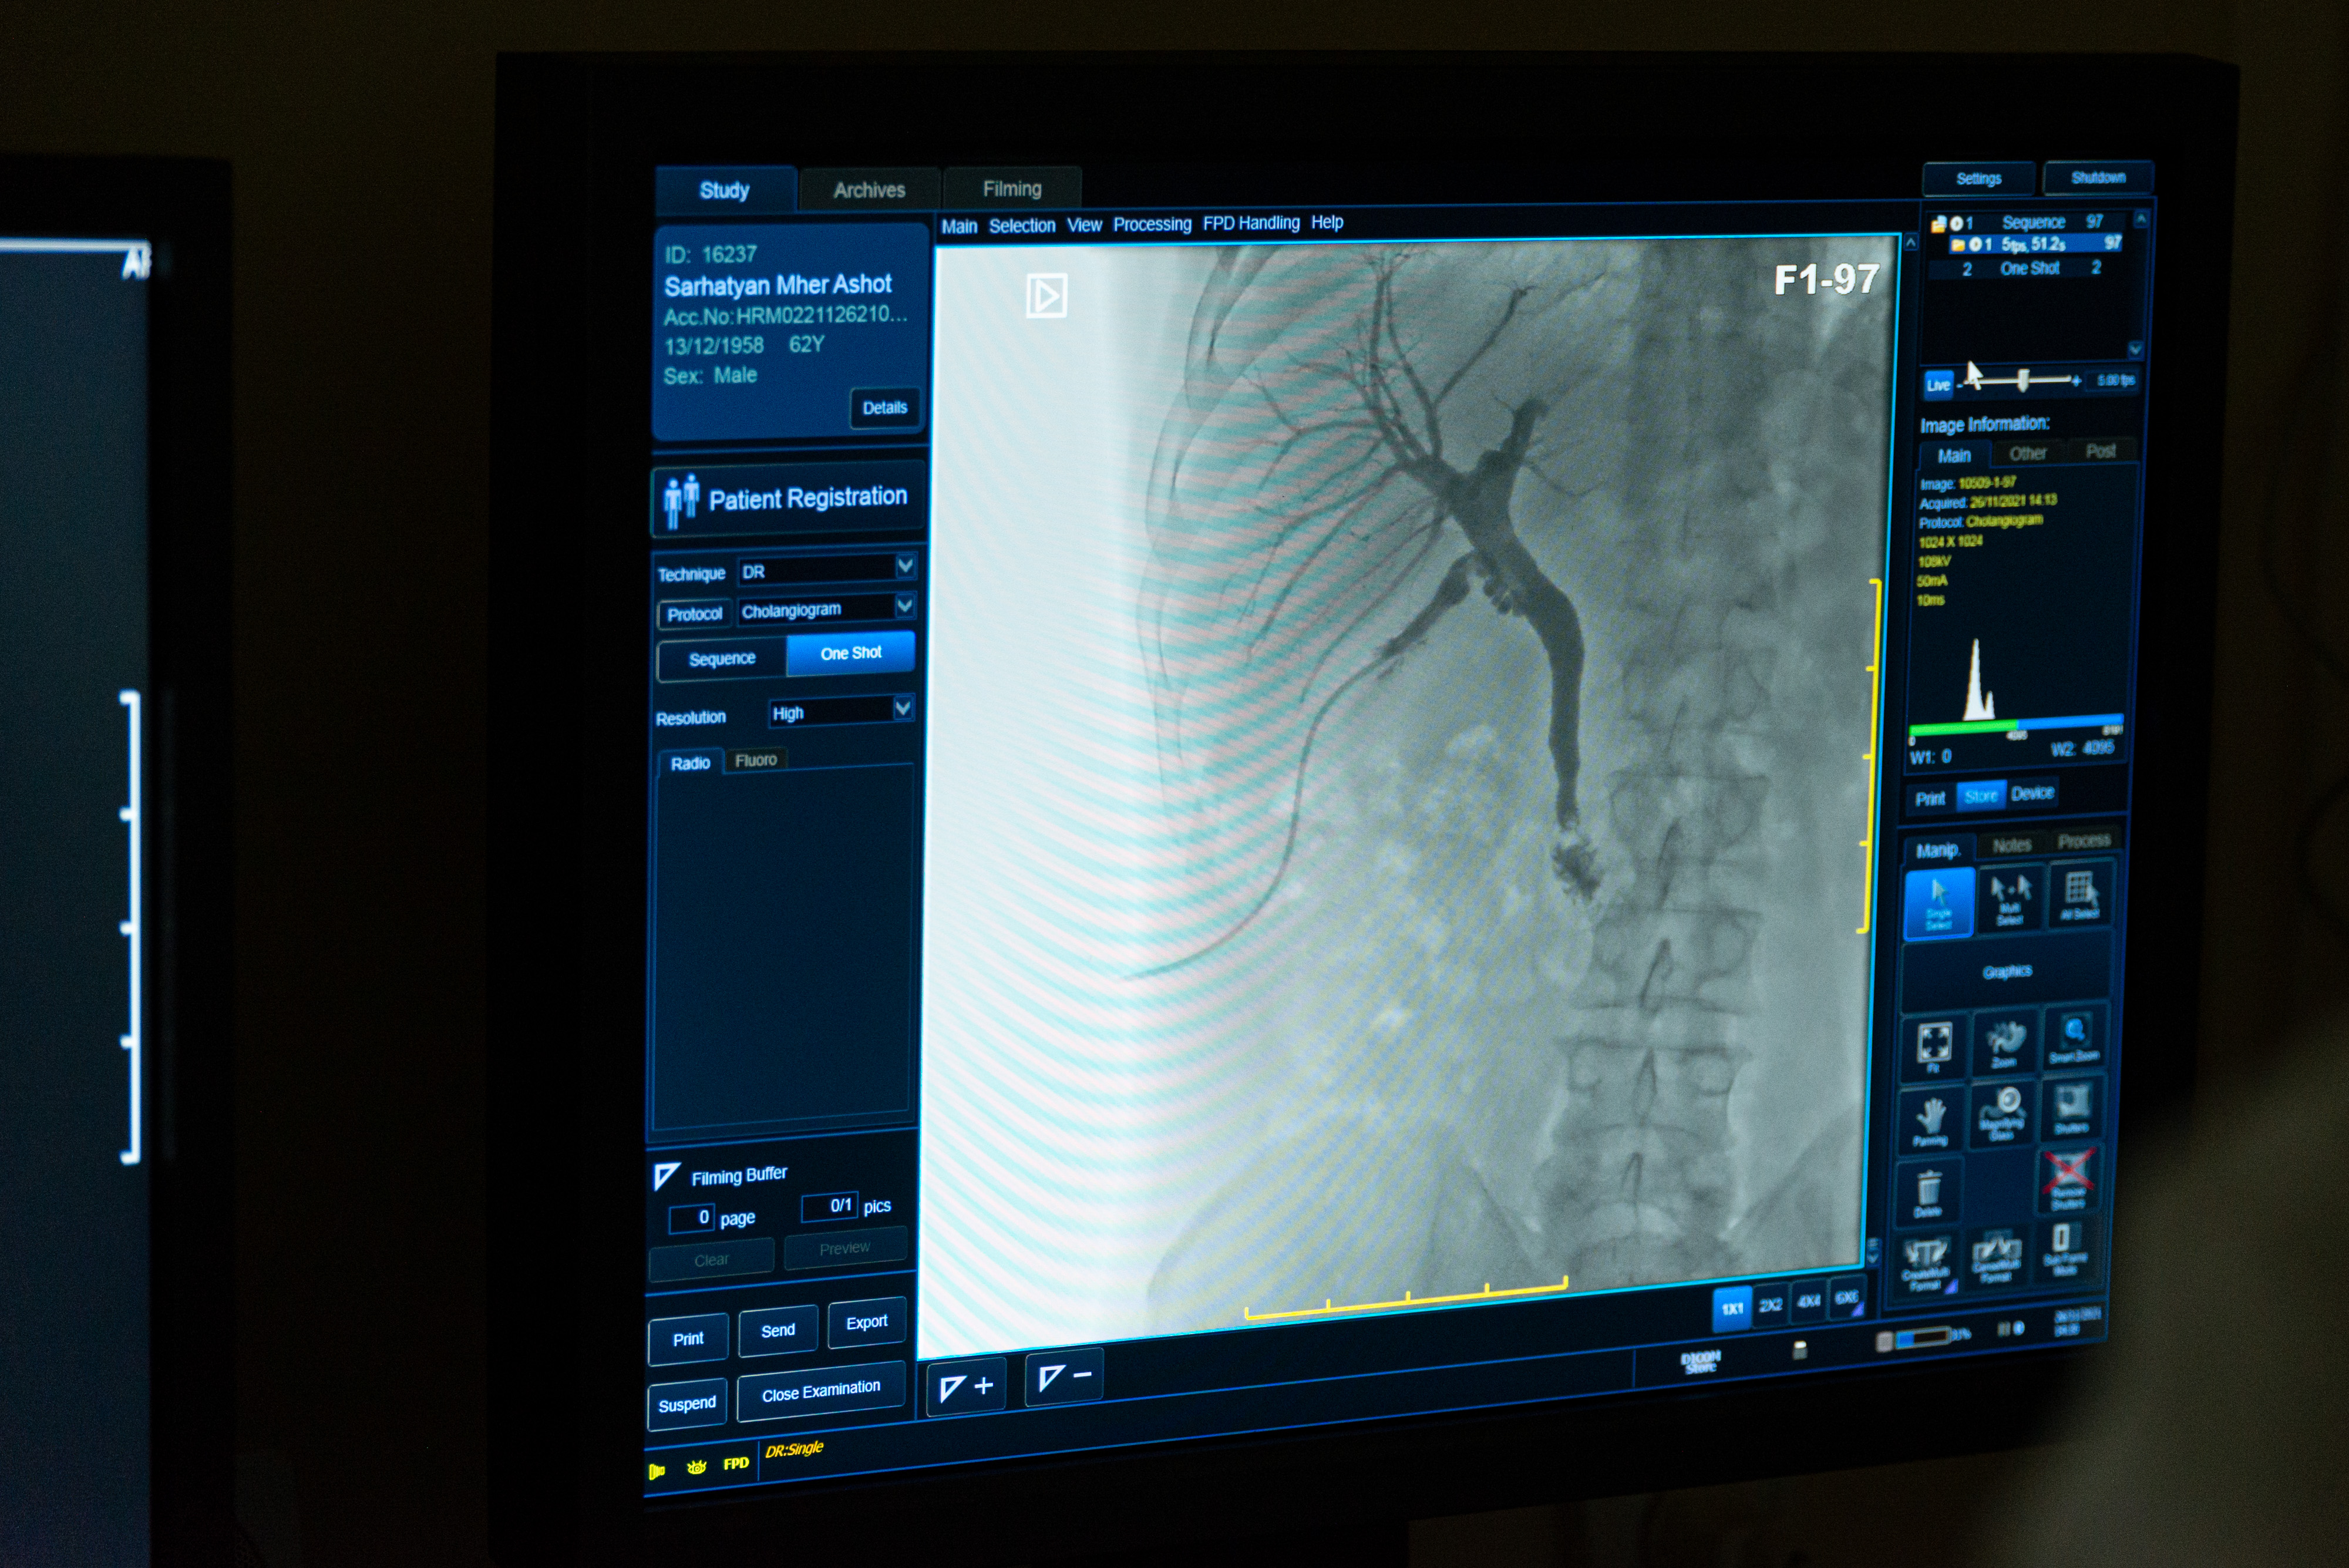

Ճառագայթային ախտորոշիչ ծառայության «Ռենտգեն» բաժնում իրականացվում են.

Ծառայությունը հագեցած է Siemens ընկերության ռենտգեն սարքով՝ թվային հավելվածով, ինչպես նաև Toshiba ընկերության համակարգչային շերտագրության սարքով: